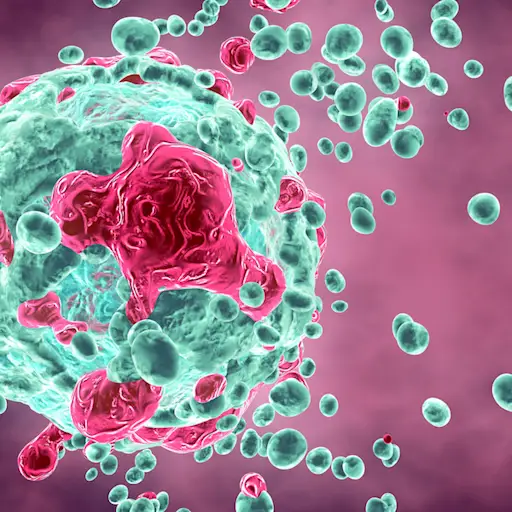

免疫疗法帮助您的身体工作更聪明,不难

肺癌治疗世界的另一个令人兴奋的发展?免疫疗法。“这与标准化疗非常不同,因为它不会自行杀死细胞 - 它实际上刺激了免疫系统来解决癌症,”Heymach博士解释道。他说,肿瘤可以聪明 - 他们学会从免疫系统中隐藏自己,因为他们在某些蛋白质中覆盖自己的覆盖。这就是免疫治疗药物进来的地方。基本上,这些药物有助于阻断这些蛋白质,因此免疫系统可以更好地看到癌症肿瘤并攻击它们。未来是现在!